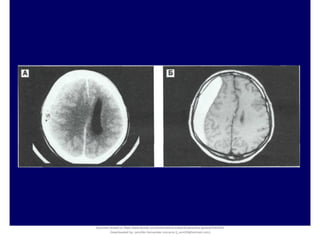

Multiple Densities of the Chronic Subdural Hematoma in CT Scans. Department of Neurosurgery, Soonchunhyang University

Cheonan Hospital, Cheonan, Korea. J Korean Neurosurg Soc 54 : 38-41, 2013